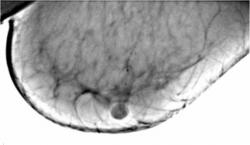

Протокол рентгенологического исследования (кратко). На снимке в прямой проекции (1) общая скиалогическая картина инволютивной молочной железы, с хорошо прослеживающимися на фоне жировой ткани соединительнотканными компонентами стромы, отдельными очаговыми уплотнениями паренхимы железы. В верхнем наружном квадранте прослеживается цепочка макрокальцинатов различной величины и формы, по расположению, напоминающая ход млечного протока, что хорошо видно также на снимке в боковой проекции (2). В верхнем внутреннем квадранте железы, а также ретроареолярно в передних отделах молочной железы определяются отдельные макрокальцинаты. На боковом снимке (2), кальцинаты, локализующиеся в верхнем медиальном квадранте группируются с образованием цепочки. «Навигатором» выделена цепочка кальцинатов, локализующаяся в верхнем наружном квадранте. При цифровой обработке в условиях «фактор» вокруг кальцинатов появляется, так называемый, «поясок безопасности».

1. Снимок в прямой проекции

2. Снимок в боковой проекции